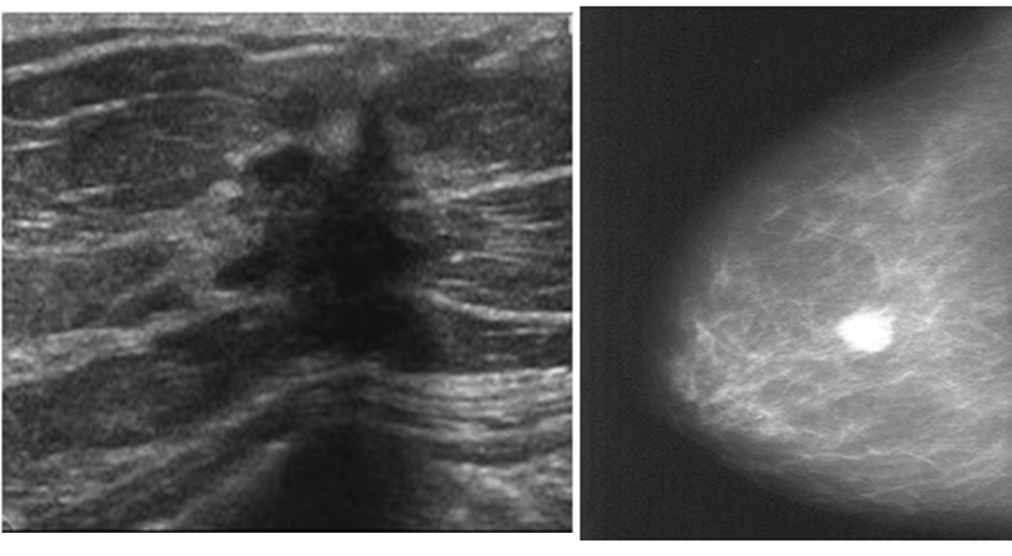

Mammography findings of benign and malignant breast lesions #Z

| Benign lesion | Malignant lesion | |

|---|---|---|

| Appearance of the lesion | - •Well-defined, circumscribed mass | - •Focal mass or density |

| Margins z | - •Surrounding radiolucent ring (halo sign) | - •Poorly defined, spiculated margins |

| Calcifications | - •Diffuse microcalcification or coarse calcification | - • Clustered microcalcifications |

| Further management z | - •Regular check-ups - •Possibly surgical excision | - •Fine needle aspiration or core needle biopsy |